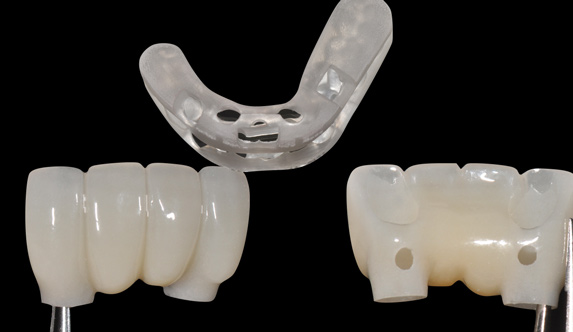

Fig 16. Presurgical design and fabrication of restorative components based on virtual implant position, allowing for possible minor angle/linear deviations (Fig 16 through Fig 18). Component options are broad and may include a custom healing abutment and bondable polymethyl methacrylate restoration; a single restoration with an engaging or non-engaging base; provisional fixed partial dentures (Fig 19), which can be indexed intraorally to prepared temporary abutments; or a full-arch restoration to be indexed intraorally to prepared temporary abutments.

Figure 16

Fig 17. Presurgical design and fabrication of restorative components based on virtual implant position, allowing for possible minor angle/linear deviations (Fig 16 through Fig 18). Component options are broad and may include a custom healing abutment and bondable polymethyl methacrylate restoration; a single restoration with an engaging or non-engaging base; provisional fixed partial dentures (Fig 19), which can be indexed intraorally to prepared temporary abutments; or a full-arch restoration to be indexed intraorally to prepared temporary abutments.

Figure 17

Fig 18. Presurgical design and fabrication of restorative components based on virtual implant position, allowing for possible minor angle/linear deviations (Fig 16 through Fig 18). Component options are broad and may include a custom healing abutment and bondable polymethyl methacrylate restoration; a single restoration with an engaging or non-engaging base; provisional fixed partial dentures (Fig 19), which can be indexed intraorally to prepared temporary abutments; or a full-arch restoration to be indexed intraorally to prepared temporary abutments.

Figure 18

Fig 19. Presurgical design and fabrication of restorative components based on virtual implant position, allowing for possible minor angle/linear deviations (Fig 16 through Fig 18). Component options are broad and may include a custom healing abutment and bondable polymethyl methacrylate restoration; a single restoration with an engaging or non-engaging base; provisional fixed partial dentures (Fig 19), which can be indexed intraorally to prepared temporary abutments; or a full-arch restoration to be indexed intraorally to prepared temporary abutments.

Figure 19